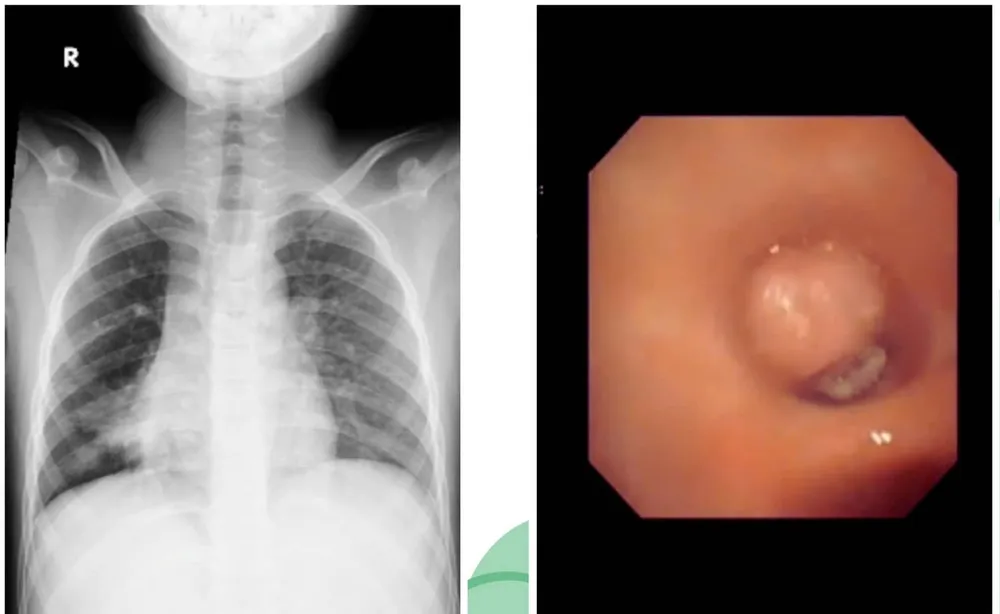

Bên trái là hình ảnh viêm xẹp thùy giữa phổi phải, bên phải là khối u ác tính ở phế quản

Khi chuyển đến Bệnh viện Nhi đồng 2 TPHCM, bác sĩ nhận định đây là tình trạng viêm phổi kéo dài trên nền bất thường cấu trúc phổi. Nội soi phế quản ghi nhận có khối u bít hoàn toàn lòng phế quản trung gian, bề mặt sần sùi. Bác sĩ tiếp tục tiến hành sinh thiết u làm xét nghiệm giải phẫu bệnh. Kết quả, khối u là carcinoma nhầy bì - một loại ung thư phổi hiếm gặp.